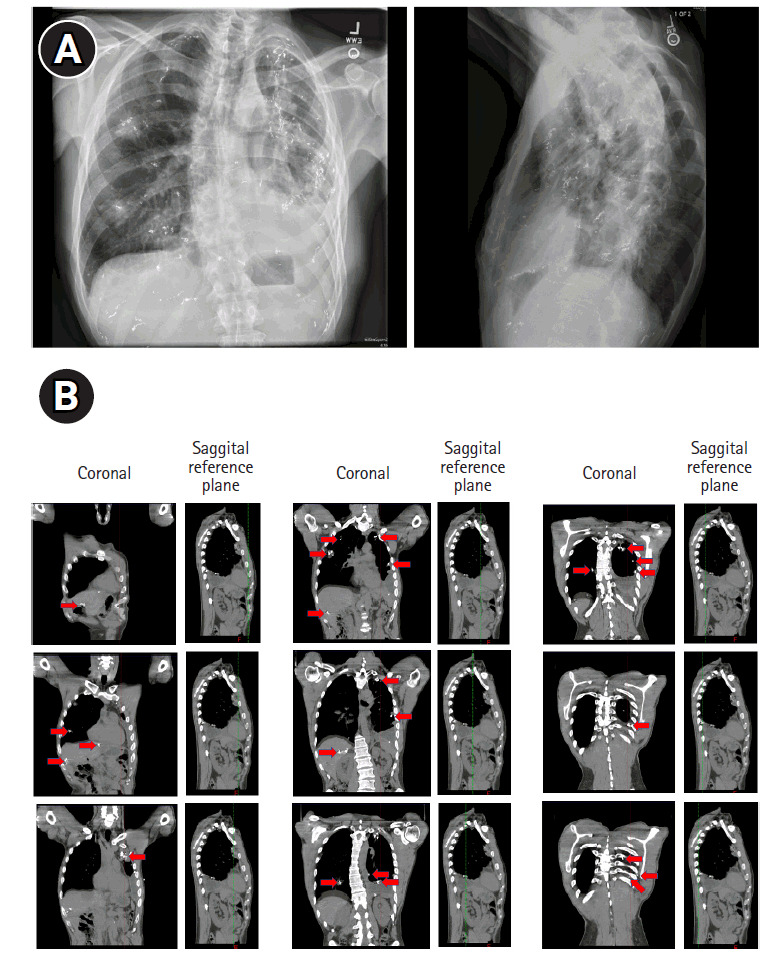

腺样囊性癌是一种难以治疗的恶性肿瘤,通常会转移到肺部。全身化疗对这种肿瘤类型无效,因此经常使用局部疗法。在此,我们报告了一个病例,该病例展示了广泛消融干预在控制转移性腺样囊性癌进展方面的应用。一名腺样囊性癌患者的肺部和肝脏出现了大量转移灶。在长达十年的时间里,他采用了包括间质近距离放射治疗和 SBRT 在内的局部消融疗法,治疗了大约 80 个不同的转移灶。该患者体内植入了 850 多颗近距离放射粒子,肿瘤控制和患者预后良好。截至 2024 年 3 月的最近一次随访,该患者自确诊腺样囊性癌以来已存活了约 12 年。据我们所知,该病例是报告的单个患者接受近距离放射治疗次数最多的病例。它凸显了间质近距离放射治疗和 SBRT 在治疗广泛的肺和肝转移瘤方面的实用性。

Adenoid cystic carcinoma is a malignancy that is difficult to treat and often metastasizes to the lung. Systemic chemotherapies are not effective for this tumor type, thus local therapies are frequently used. Here, we report a case demonstrating the use of extensive ablative interventions in controlling the progression of metastatic adenoid cystic carcinoma. A patient with adenoid cystic carcinoma developed numerous metastases to his lungs and liver. Local ablative therapies including interstitial brachytherapy and SBRT were used to treat approximately 80 different metastases over the course of a decade. Over 850 brachytherapy seeds were implanted in this patient, and the tumor control and patient outcome were good. As of the most recent follow-up in March 2024, the patient has survived for approximately 12 years since his diagnosis of adenoid cystic carcinoma. To our knowledge, this case represents the most brachytherapy treatments reported in a single patient. It highlights the utility of interstitial brachytherapy and SBRT in treating extensive lung and liver metastases.